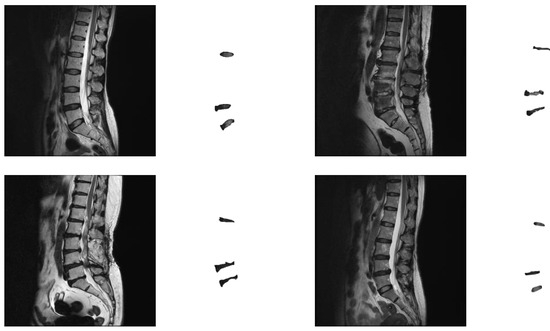

2.3.3. The Data-Augmented Segmentation Method

Figure 5. (a) An example of an original image augmented with the distance maps. (b) The training and prediction flow chart of the data-augmented segmentation method.